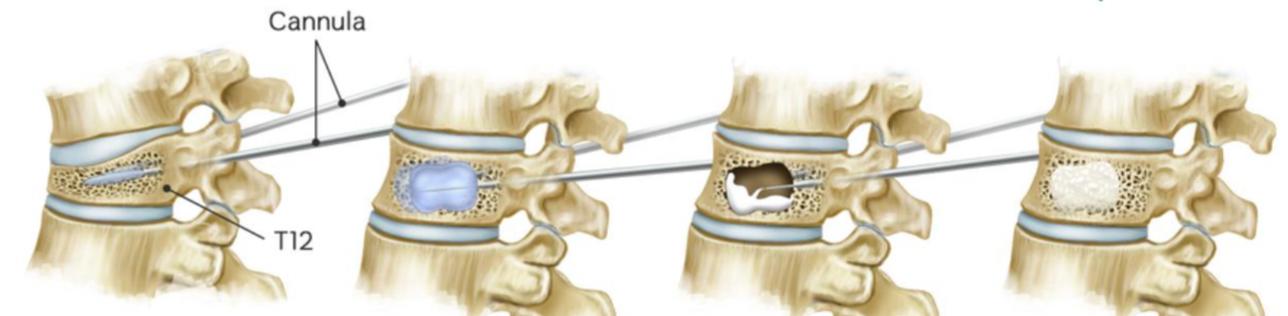

Steps

1. OperativeLevelIdentificationandimageguidance(using end-ontechniquedescribedpreviously):

a

b

LateralImaging:Superimposeanatomy,includingthe pediclesandendplates Asatisfactorylateralimagewill reflectclearvisualisationofthepedicleandforamenas wellasthesuperior,inferior,anteriorandposterior aspectsofthevertebralbody

3 Needleadvancement: Needlestartsatteno’clockmarkon theleftsideandtwoo’clockmarkontherightside(clockfaceanalogy) Theneedleisthenadvancedtothemedial borderofthepedicleandalateralfluoroscopicimageis obtained Oncethetipoftheneedleisconfirmedtobe anteriortotheposteriorvertebralmargin,itisfurther advancedintotheposteriorone-thirdofthevertebralbody Thisisrepeatedontheoppositeside.

SkinIncision:Incisionlateraltothelateralpedicularborder Whencontactwithboneismade,theneedleshouldbeatthe superolateralaspectofthepedicle.

5 Balloondeployment: ballooncathetersareinsertedthrough theaccesscannulasandsubsequentlydeployed Again, imagesaretakentoconfirmcorrectballoonplacement

Confirmationofplacement:Onceaccessthroughthe pedicleshasbeenachieved,ahanddrillisusedocreatea channelforthesubsequentballoons APimageistakennow toconfirmplacement. Thisisrepeatedontheoppositeside.

6 Ballooninflationandcementinjection: Balloontampsare advancedbilaterally Eachballoontamp,attachedtoa lockingsyringewithadigitalmanometer,istheninflatedwith iodinatedcontrast APandlateralimagesareobtained duringinflationtoguaranteesafeandproperepansionand fracturereduction Onceexpansionisadequatelyperformed, balloonsaredeflatedand injectionofcementiscarriedout (cementcannulaisintroducedintoaccesscannulaforthis step). Enoughcementtofillvoidcreatedbyballoonsshould beinjected

Completionofprocedure:cementcannularemovedand styletneedleintroducedintoworkingcannula Oncecement hassecured,cannulais removedunderconstantimagingto detectanyposteriormigrationofcement

Figure14:IllustrationofKyphoplastyprocedure A)lateralfluoroscopicimagesofbonecementcannula insertion(topleft),ballooninflation(topright),bone cementevenlydistributedinvertebralbody(bottomleft), APviewofbilateralballoonkyphoplasty(bottomright) B)simplifiedillustrationofprocedure;needleadvanced intovertebralbody(topleft),ballooninflated(topright), balloondeflatedandcementinjected(bottomleft), cementin-situ(bottomright)